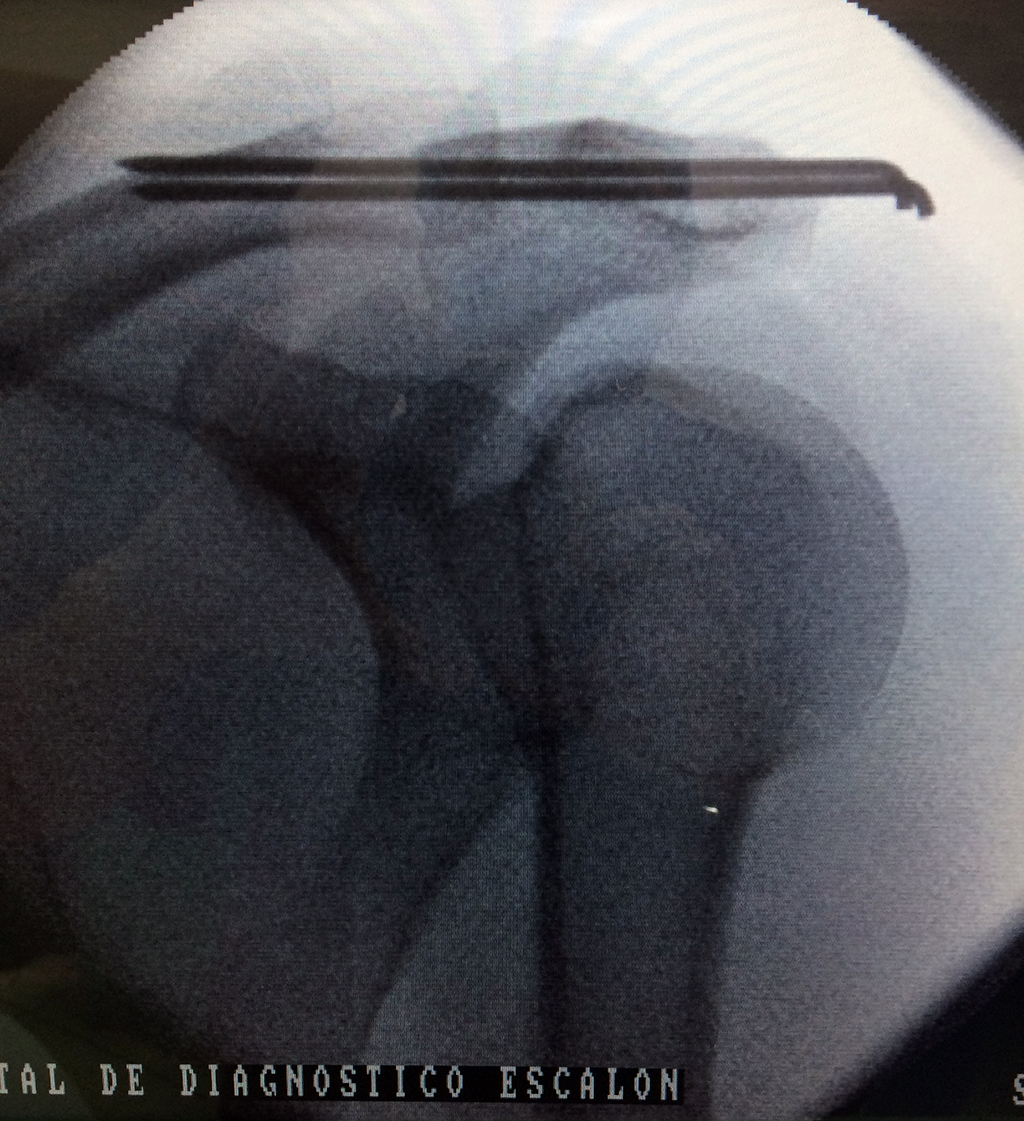

Cirugía de Fémur - Clavícula

La clavícula es un hueso largo, con forma de "S" itálica, situado en la parte anterosuperior del tórax. Junto con la escápula forman la cintura escapular. Se puede palpar por toda su longitud y se extiende del esternón al acromion de la escápula, siguiendo una dirección oblicua lateral y posterior.